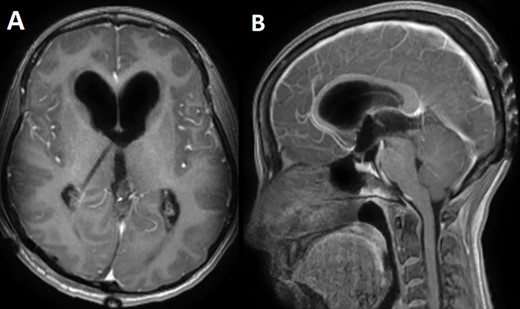

A 33-year-old lady presented to the clinic for bilateral retro-orbital headache with tinnitus most severe upon waking up in the morning for 3 months, without evidence of nausea, vomiting, or insomnia. Vital signs were within the normal range. The neurologic exam was non-focal. Enhanced brain magnetic resonance imaging (MRI) revealed a T1 hypointense, T2 hyperintense, homogenously enhancing Pineal tumor of 2 × 1.89 × 1.61 cm (anteroposterior × transverse × height) compressing the posterior wall of the third ventricle with evidence of moderate hydrocephalus (Fig. 1). The patient was scheduled for craniotomy for resection of the mass. In the operating room, an external ventricular drain was inserted in the right occipital horn followed by craniotomy and resection of the mass through a right occipital transtentorial approach. Gross total surgical resection was achieved under microscopic navigation (Fig. 2). The patient was extubated. Upon extubation the patient started to have chewing-like movement of her lips on the ET tube, afterward, she was transferred to the intensive care unit for monitoring. On postoperative day 1, we noticed that the patient was still having chewing-like movements typical of orofacial dyskinesia with evidence of buccal mucosal injury and swelling of the lips (Video 1). She was also complaining of inability to sleep. The patient was on regular postoperative medications (esomeprazole, cefazolin, paracetamol, morphine, dexamethasone, levetiracetam). An enhanced postoperative brain MRI was done for evaluation and confirmed complete resection of the lesion without any bleeding or ischemic changes (Fig. 3). The chewing like movements lasted for 72 hours and spontaneously resolved afterward. Pathology confirmed pineal parenchymal tumor of intermediate differentiation (WHO Grade III). The patient was treated with adjuvant radiotherapy. This is an unreported complication post pineal gland tumor resection in humans. Below we review the literature reporting abnormal facial movements associated with various pineal gland conditions as the data remains scarce concerning dyskinesia post pineal tumors resection in humans.

A postoperative day 1 T1 enhanced axial (A) and sagittal (B) MRI confirming complete surgical resection of the pineal tumor.